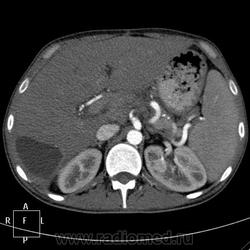

КТ (часть кадров выложу позже ). Цель направления на КТ - образование правой доли печени, исключить образование тела п.ж.

). Цель направления на КТ - образование правой доли печени, исключить образование тела п.ж.

В данном случае ранняя артериальная получилась с брачком - контрастировалась нижняя полая (25 сек задержка, триггера нет), панкреатическая 45 сек (стандарт), портальная 70 сек. Отсроченная в печени делается на подозрение на холангиокарциному и гемангиому. Тут почки и не интересовали.

Гемангиома, являясь сосудистой опухолью, будет такого же цвета, как и сосуды, во все фазы. Это - кистовидное образование, стенки относительно равномерной толщины, копящие контраст тонкой полоской. Содержимое образования жидкостной плотности и контраст не копит.

Гепатоспленогмегалия. Начальная портальная гипертензия, холедох не расширен. В воротах печени бугристая масса.... чего? Кальцинаты поджелудочной железы, мелкий камушек в желчном. Вопрос в том, что за кистовидное образование, что за полоса-серп вокруг желчного пузыря, что в воротах печени. Опухоли п.ж. я не нашла.

Данному пациенту в заключении я выставила подпеченочный абсцесс, гепатоспленомегалию, портальную гипертензию, конгломерат лимфоузлов ворот печени, лимфаденопатию желудочной группы л/у, хр.калькулезный панкреатит, ЖКБ с перихолециститом.

В воротах, похоже л/у, а жидкостное абсцесс печени.

Абсцесс печени.